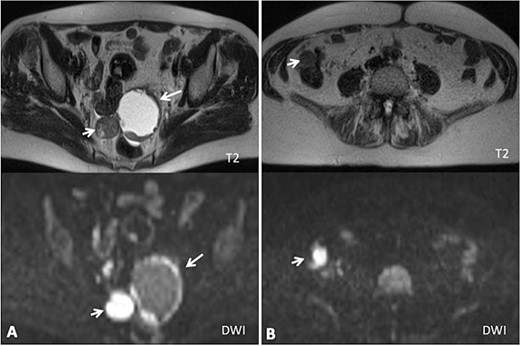

A 68-year-old patient, initially diagnosed with a FIGO stage IIA fallopian tube carcinoma, was under active follow-up in the Gynecologic Oncology Clinic at our institution since 2020. She underwent primary cytoreductive surgery in August 2019 (hysterectomy, bilateral salpingo-oophorectomy, omentectomy, pelvic and para-aortic lymphadenectomy, without any residual macroscopic disease) and completed six cycles of postoperative chemotherapy (carboplatin and paclitaxel) in January 2020. She was free of disease until May 2022 (disease free interval—26 months) when her CA 125 began to rise (52 U/L). CT and MRI scans showed splenic and subcapsular hepatic implants, two metastatic pelvic nodules with 31 and 58 mm next to the sigmoid colon and rectum, and several mesenteric implants in the descendent colon (Figs 1 and 2).

(A) Axial MRI imaging showing the pelvic tumor implants; (B) axial MRI imaging showing the implants in the right colon (diffusion weighted imaging).